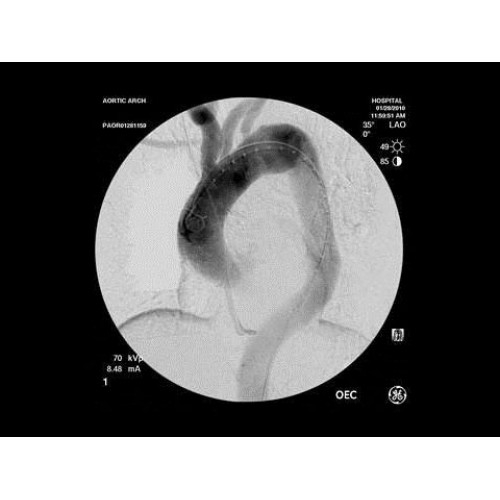

Инновационная мобильная С-дуговая система для интраоперационной визуализации с высоким разрешением. Обеспечивает хирургов качественным изображением в реальном времени при минимальной лучевой нагрузке. Усовершенствованная эргономика позволяет легко позиционировать аппарат в условиях операционной. Поддерживает интеграцию с современными хирургическими навигационными системами.

Передовая рентгенохирургическая система GE OEC 9900 Elite представляет собой инновационное решение для проведения широкого спектра малоинвазивных вмешательств. Это оборудование премиум-класса сочетает высочайшее качество визуализации с интуитивно понятным управлением, устанавливая новые стандарты в области интраоперационной рентгеноскопии.

GE OEC 9900 Elite оснащен революционной системой визуализации, обеспечивающей кристально четкое изображение анатомических структур. Интеллектуальная система автоматически адаптирует параметры исследования под конкретную хирургическую задачу, обеспечивая оптимальный баланс между качеством изображения и лучевой нагрузкой. Особое внимание уделено удобству работы операционной бригады.

• Кардиохирургические вмешательства и ангиопластика

В ведущих медицинских центрах GE OEC 9900 Elite успешно применяется для проведения сложных кардиологических, нейрохирургических и ортопедических вмешательств. Система доказала свою эффективность при выполнении стентирования коронарных артерий, эмболизации сосудов головного мозга и вертебропластики. Многие учреждения отмечают повышение качества операций после внедрения этого оборудования.